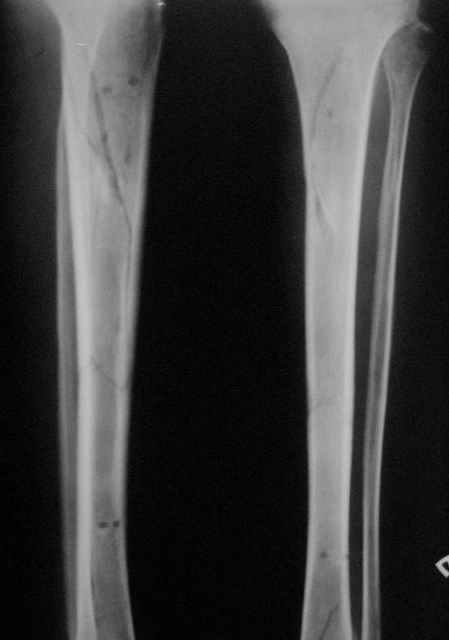

Открытый (2 В Каплан) многооскольчатый перелом левого бедра. Перелом межмыщелкового возвышения большеберцовой кости без смещения слева. Открытый (1 А Каплан) перелом с/3 -н/3 костей правой голени, перелом пяточной кости справа.На седьмые сутки выполнены операции:1. ЗИМО (статически, Chm-CHARFIX) левого бедра. 2. Остеосинтез стержневым аппаратом костей правой голени и пяточной кости. См. r-gr.На сегодня аппарат демонтирован, больной ходит с ограниченной нагрузкой.Смущает стояние отломков в верхней трети бедра (как то не задумались при планировании операции о реконструктивном или гамме штифте ) хватит ли этих двух винтов для стабильности?С Уважением Владимир Бахарев.

Длина проксимального отломка тут достаточна для использования любого диафизарного гвоздя, так что в этом отношении как раз все в порядке. Запас прочности, однако, тут для ранней полной нагрузки недостаточен, и даже с реконструкционным было бы немногим больше - дистальные винты те же 4,5 мм, а они у гвоздей ChM довольно хлипкие. Так что с нагрузкой тут лучше не спешить до уверенных признаков пластики на снимках.

Видна заметная наружная ротация центрального отломка. Если это не случайно сделали снимок, не выведя колено в нейтральное положение, то это типичное смещение, если делать синтез на тракционном столе с тазовой подставкой и промежностным упором. Стоило бы сделать снимок обоих тазобедренных суставов при одинаково уложенных коленных. Для этой же цели можно сделать и снимок в сгибании 90 градусов коленых и тазобедренных суставов, будет прямо видно